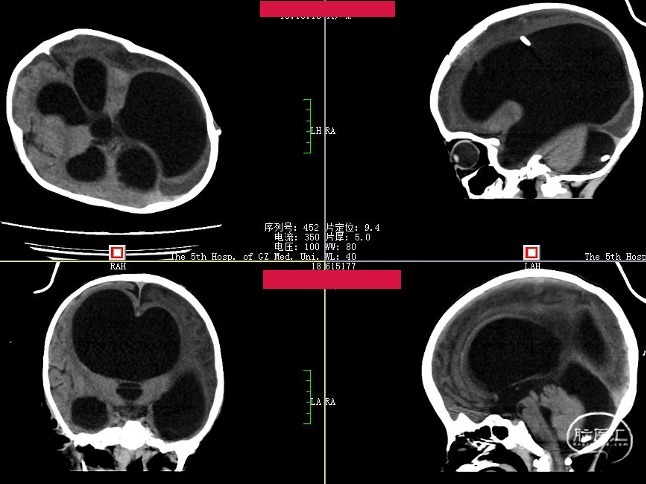

术前头颅CT

Evans index(EI)≈0.5